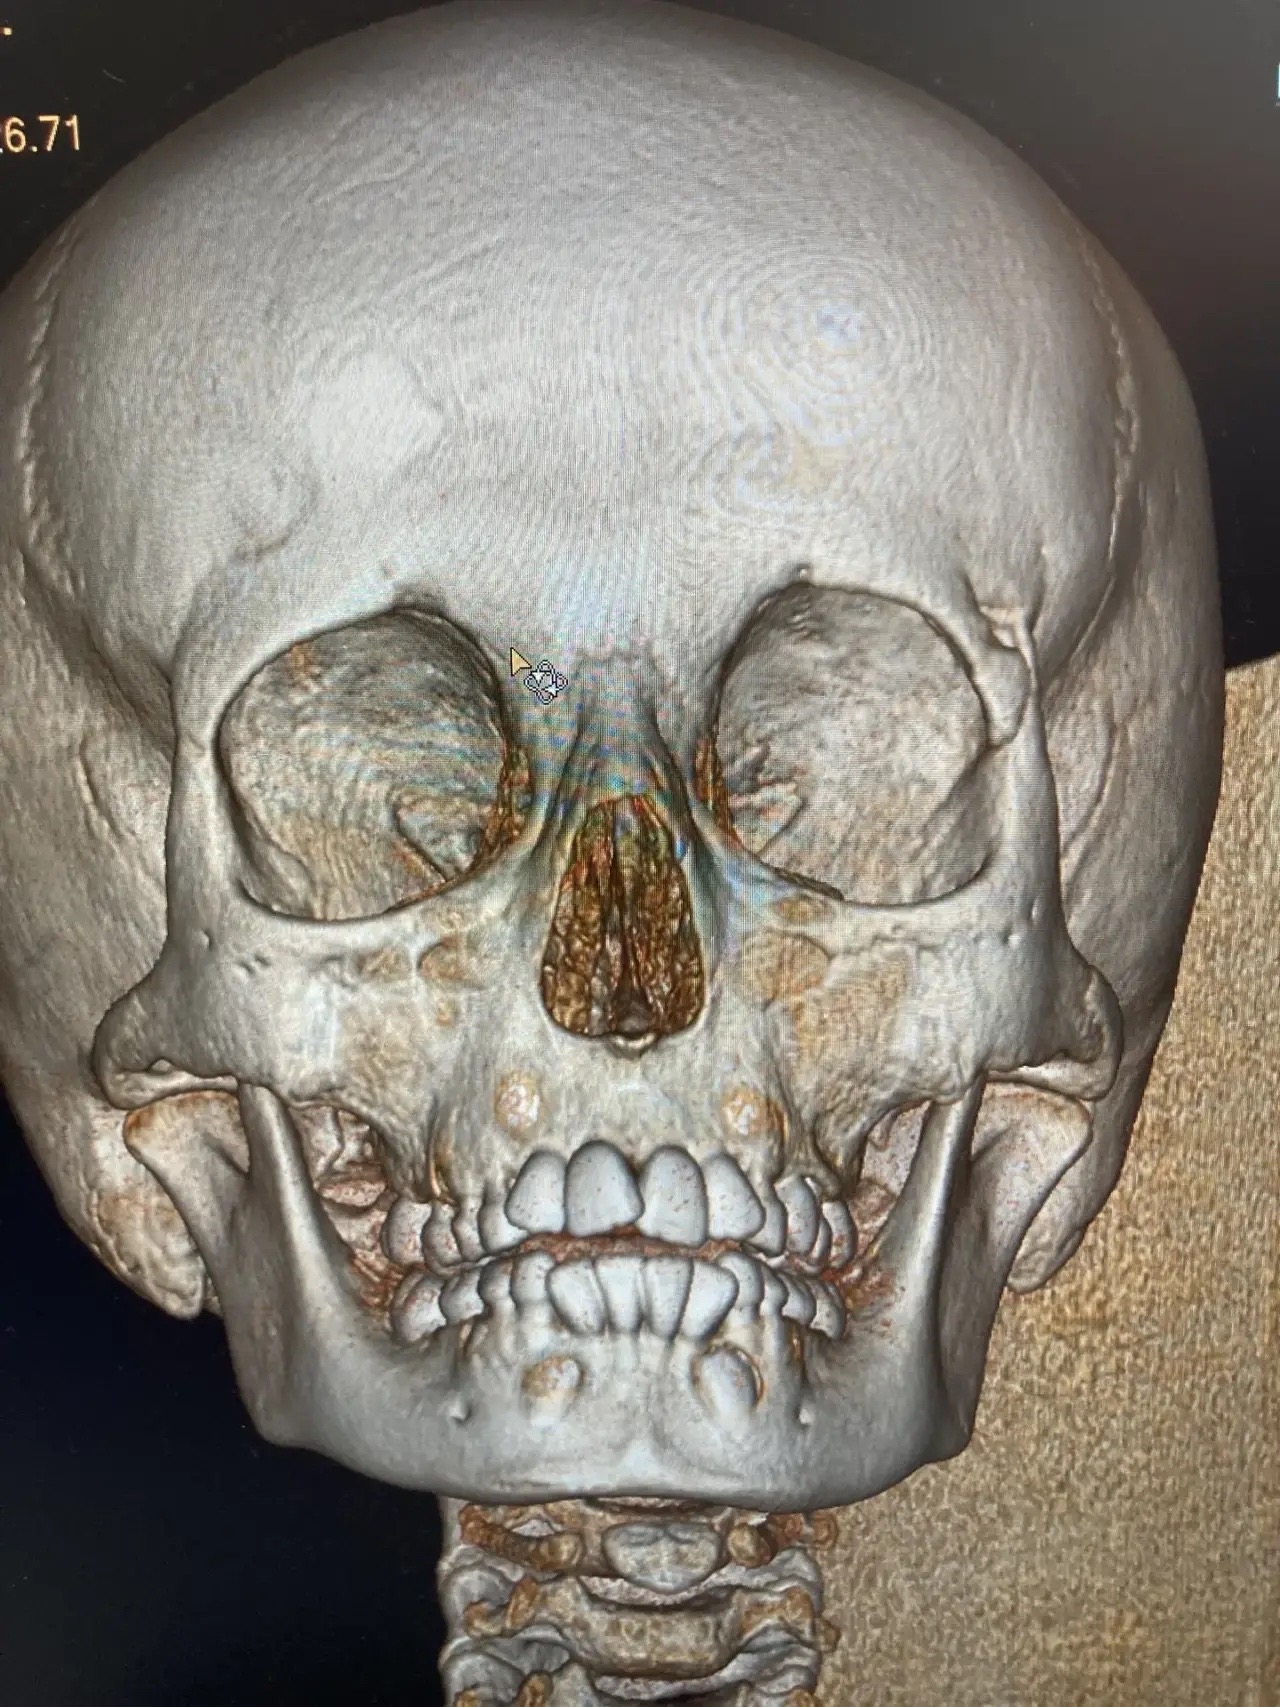

Врачи ОДКБ успешно провели операцию 8-летней девочки, на которую упала ледяная глыба. Несчастный случай произошел в Кольчугино на улице Кима 20 марта. Ребенка экстренно госпитализировали с черепно-мозговой травмой и сложным переломом в области верхнего края левой глазницы.

Один из осколков кости сместился внутрь и повредил глазное яблоко. Ребёнка доставили в Областную детскую клиническую больницу, в хирургическое отделение №1. Как рассказывают врачи, операция потребовала от врачей максимальной точности и слаженности действий: необходимо было не только восстановить правильное положение костных фрагментов, но и устранить повреждение глаза.

Хирурги ювелирно выполнили репозицию перелома, вернув костям анатомически верное положение, и провели ушивание раны глаза. Операция прошла успешно. Сейчас девочка находится под постоянным наблюдением специалистов, получает всю необходимую терапию и уход. Её состояние стабильно, врачи делают всё возможное для скорейшего восстановления.